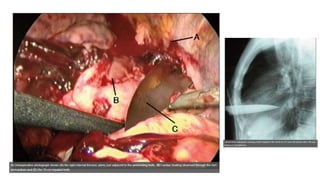

A) TAC muestra bronquio izquierdo principal deformado; discontínuo

con aire alrededor de bronquios; además NT derecho y enfisema

subcutáneo al ingreso;

C tras día 50 TAC atelectasia izquierda e interrupción total bronquio

principal izquierdo.

• D y E imágenes

transquirúrgicas –

bronquio resecado

posteriormente

anastomosis

A) TAC muestrabronquio izquierdo principal deformado; discontínuo con aire alrededor de bronquios; además NT derecho y enfisema subcutáneo al ingreso; C tras día 50 TAC atelectasia izquierda e interrupción total bronquio principal izquierdo.

• D yE imágenes transquirúrgicas – bronquio resecado posteriormente anastomosis • F TAC posqx muestra expansion pulmón izquierdo y desbloqueo bronquio principal y bronquios lobares